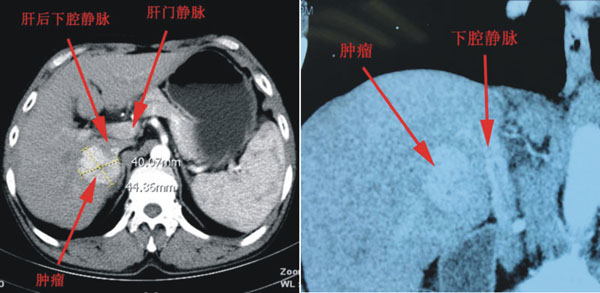

患者是一名来自澄县的52岁男性,在当地医院诊断为原发性肝癌、乙肝肝硬化。肿瘤大小约4.5×4×4cm,位于肝脏Ⅵ、Ⅶ段之间,紧贴肝后下腔静脉,前方是第一肝门,上方毗邻第二肝门,右侧有门静脉右后支及胆道跨过,解剖部位非常复杂,是肝脏手术的相对禁区。且患者有慢性肝病,肝储备功能差,难以耐受半肝切除手术,所以手术既要保证肝癌的根治性切除,又要考虑患者术后肝功能的恢复,手术风险大,成功率很低,如术中稍有不慎可能会造成难以挽救的后果。因此之前患者辗转西安多家医院均被告知手术难度大,建议转院。黎一鸣教授接诊该患者后,经过慎重的的评估,认为手术切除的的机会较大。入院后,针对患者的病情及影像学资料,普外科对患者拟定了精密的手术规划,并做了精细的术前准备。

术前增强CT及冠状位重建检查